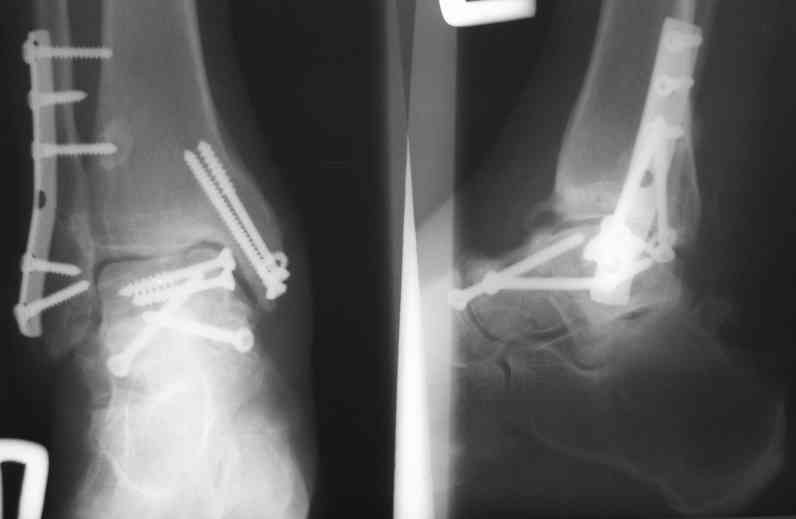

И второй случай из недавней ташкентской практики, (извините за качество ренгенограммы и только в одной проекции) случай падения с высоты (кстати моего друга - известного киноактера) - открытый

смещенный перелом тарана, с переломом переднего края дистального эпиметафиза большеберцовой кости.

При поступлении в приемной сделана первичная обработка с ушиванием открытой латеральной раны и вытяжением за пятку.

Из-за отсутствия времени пришлось оперировать на второе утро, из материала, что имеем на месте, фиксирован двумя шурупами, а третий-это контур сломанного жойстика в 4 мм. На дистальный медиальный конец тибиа antiglide 3.5 мм пластина. Через пару дней выписан и несмотря на предупреждение, самостоятельно начал нагрузку в 4 недели, время не ждет, снимается в боевике в Росийской Федерации.

Djoldas Kuldjanov, MD